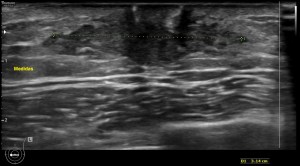

Aquí en la imagen 3 y 4 observas claramente como en el espacio retroareolar observamos una imagen hipoecogénica más larga que alta, heterogénea que está ocupando lo que normalmente debería ser espacio de grasa normal. En la imagen 4 lo que hacemos es realizar las medidas pertinentes, en los planos que consideremos oportunos.